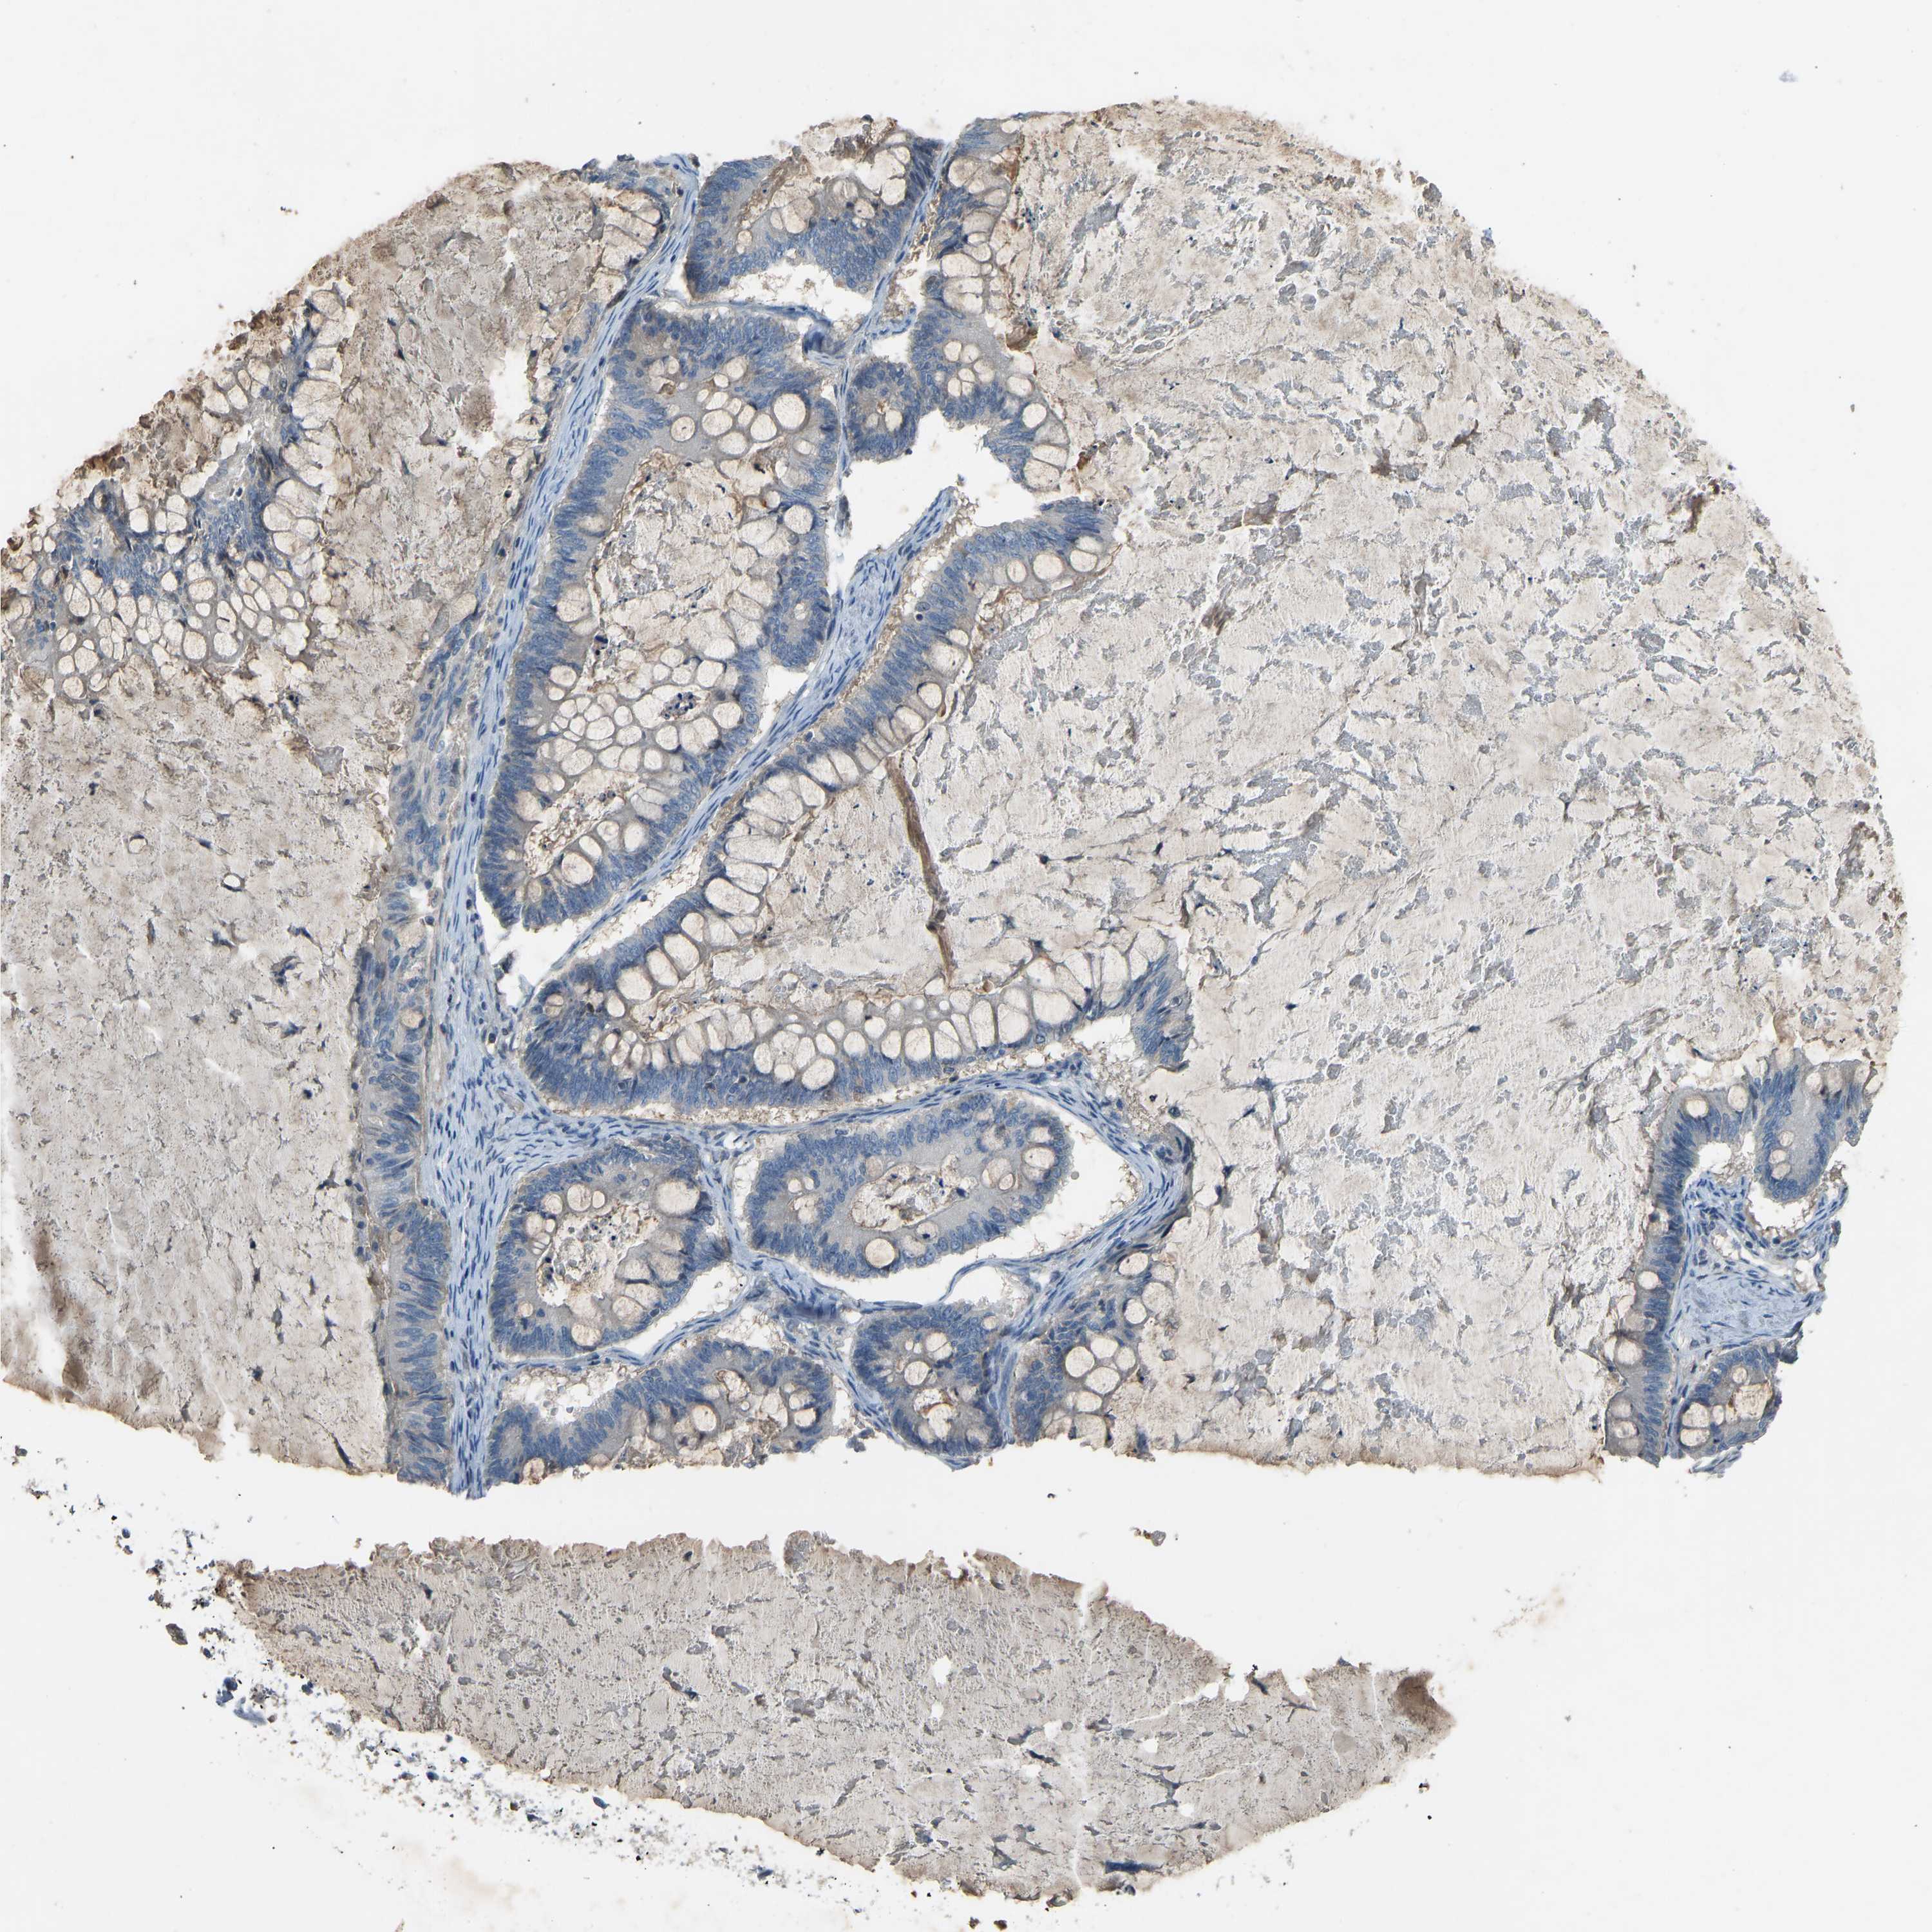

OVARIAN CANCER - Protein expressioni

A mouse-over function shows sample information and annotation data. Click on an image to view it in a full screen mode. Samples can be filtered based on level of antibody staining by selecting one or several of the following categories: high, medium, low and not detected. The assay and annotation is described here.

Note that samples used for immunohistochemistry by the Human Protein Atlas do not correspond to samples in the TCGA dataset.

Antibody stainingi

Antibody staining in the annotated cell types in the current human tissue is reported as not detected, low, medium, or high, based on conventional immunohistochemistry profiling in selected tissues. This score is based on the combination of the staining intensity and fraction of stained cells.

Each image is clickable and will lead to virtual microscopy that enables deeper exploration of all samples and also displays staining intensity scores, fraction scores and subcellular localization as well as patient and tissue information for each sample.

Antibody HPA001934

Antibody CAB018622

Cystadenocarcinoma, mucinous, NOS

Carcinoma, endometroid

Cystadenocarcinoma, serous, NOS

Carcinoma, NOS